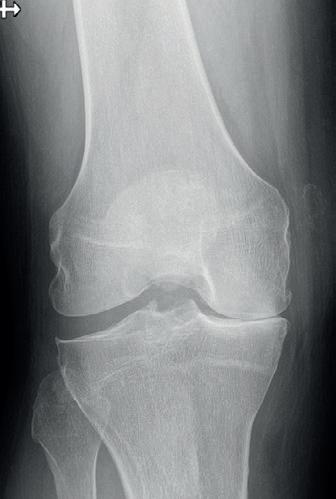

Foto 2 Standaard preoperatief radiografisch bilan. Het betreft hier een eindgradige (cfr Schuss opname) variserende gonarthrose bij onderliggend varus alignement (loodlijn van centrum heupkop naar centrum enkelgewricht loopt door mediaal compartiment op full leg opname). Gezien reeds eindgradige artrose is dit dus geen ideale casus voor osteotomie maar zal eerder voor unicondylaire knieprothese geopteerd worden.

Indicatie wordt gesteld aan de hand van standaard radiografisch bilan. Deze bestaat uit de 4 standaard opnames (face/profiel/ schuss en axiaal) en een Rx full leg opname bilateraal waarop het alignement van de patiënt wordt bepaald (foto 2). Aan de hand van hoekmetingen kan dan bepaald worden waar de afwijking zich bevindt (tibia of femur) en waar de correctie dus dient te gebeuren. Idealiter betreft het een jonge patiënt met een milde tot matige gonartrose volgens classificatie van Kellgren-Lawrence. (foto 3) Resultaten bij een eindgradige (= graad 4) artrose zijn onvoorspelbaar en uitstel naar prothesechirurgie vaak beperkt. Daarom wordt er op dat moment soms beter geopteerd voor een unicondylaire knieprothese.